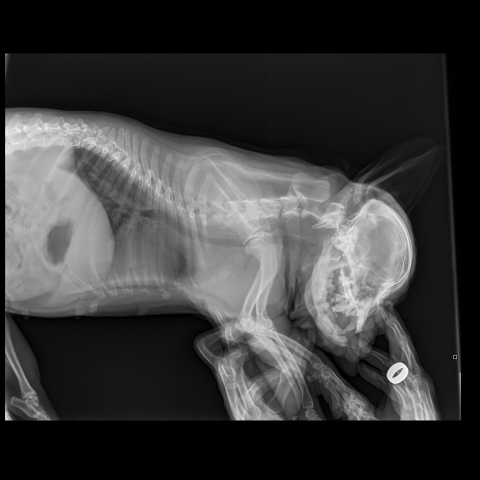

Снимки хорошие, качественные, но совершенно не информативные. На этих пленках патология не определяется. Но здесь нет снимка, который нужен обязательно - поясничный отдел позвоночника в прямой проекции (такой, как 3-й, но только не шея, а поясница).

Нет,наоборот.Собака сначала стала немного наклонять голову вправо.Когда были на консультации у окулиста,то он обратил внимание на это ,сказал,что есть какие-то изменения в области шеи.Я отсутствовала дома 2 недели.Приехала,собаку вообще не узнала.Крен головы вправо стал еще сильнее,передние ноги как-то ослабли.Она идет,может споткнуться,упасть.Сходили,сделали рентген.снимок.Поставили диагноз:атланто-аксиальная нестабильность шейного отдела,спондилоартроз. Проколола 5 дней:актовегин,папаверин,комбилипн,мидокалм,дексаметазон. Пока делала уколы и еще дней 5 после этого собаке стало легче,а потом опять вернулись к тому, что было.На консультации врач сказал,что дальше просто колоть преднизалон. Я уехала к другому врачу,тот сделал снимки,которые я Вам отослала.Сказал, что диагноз не подтверждает,на пальцах показал, что со спинным мозгом все нормально.С помощью какой-то процедуры (бумаги на работе)обнаружил перфорацию барабанной перепонки.Выписал лечение:цефтриаксон,циклоферон,цебролизин(колола 2 дня,стало хуже),комбилипен.В уши-изотик.Сказал,что может быть у собаки был инсульт.Собаке от лечения хуже.Вот такие дела.